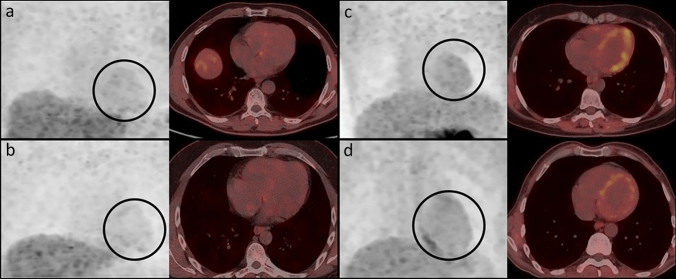

Forty patients (17 with Parkin, 3 with DJ-1 mutations and 20 with IPD) were included. Striatal dopaminergic innervation was assessed semi-quantitatively by 18F-DOPA PET, and cardiac 18F-DOPA uptake was also evaluated. Brain 18F-FDG PET images were evaluated visually. Resting-state functional MRI and diffusion tensor imaging (DTI) were used to assess the BGN activity and WM microstructural alterations.

AR-PD patients showed significantly decreased 18F-DOPA uptake in caudate corpus compared to both IPD and controls, with a more symmetrical striatal dopaminergic denervation. Myocardial 18F-DOPA uptake in AR-PD was similar to controls, while it was significantly reduced in IPD. There was no significant difference in cortical 18F-FDG metabolism and functional activity of BGN between PD groups. The DTI data revealed more extensive WM microstructural damage in AR-PD compared to IPD.

AR-PD group showed additional significant decreased 18F-DOPA uptake in caudate corpus and more symmetrical striatal denervation. Additionally, relatively preserved myocardial innervation, cortical metabolic and WM microstructural changes suggest the possibility of “brain-first” type progression in AR-PD. Also, 18F-DOPA PET/CT may be a practical tool for evaluating dopaminergic innervation of striatum and heart together, but further evaluation is needed in this area.